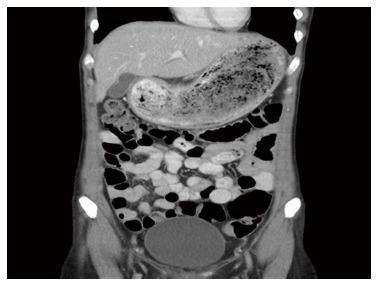

Recurrent Rapunzel syndrome (RRS) is a rare clinical presentation with fewer than six cases reported in the PubMed literature. A report of RRS and literature review is presented. A 25-year-old female was admitted to hospital with a 4-wk history of epigastric pain and swelling. She had a known history of trichophagia with a previous admission for Rapunzel syndrome requiring a laparotomy nine years earlier, aged 16. Psychological treatment had been successfully achieved for nine years with outpatient hypnotherapy sessions only, but she defaulted on her last session due to stressors at home. The abdominal examination demonstrated an epigastric mass. Computer tomography scan revealed a large gastric bezoar and features of aspiration pneumonia. The patient underwent emergency open surgical laparotomy for removal as the bezoar could not be removed endoscopically. The bezoar was cast in a shape that mimicked the contours of the stomach and proximal small bowel, hence the diagnosis of RRS. The patient was seen by a psychiatrist and was commenced on Quetiapine before discharge. She continues to attend follow-up.

复发性长发公主综合征(RRS)是一种罕见的临床表现,在PubMed文献中报道的病例少于6例。本文呈现了一例RRS病例报告及文献综述。一名25岁女性因上腹部疼痛和肿胀4周病史入院。她有吞食毛发的病史,16岁时曾因长发公主综合征入院,9年前需要进行剖腹手术。仅通过门诊催眠治疗成功进行了9年的心理治疗,但由于家庭压力因素,她未能参加最后一次治疗。腹部检查发现上腹部有肿块。计算机断层扫描显示有一个大的胃石以及吸入性肺炎的特征。由于胃石无法通过内镜取出,患者接受了急诊开放性外科剖腹手术以将其取出。胃石的形状模仿了胃和近端小肠的轮廓,因此诊断为RRS。患者在出院前由精神科医生诊治并开始服用喹硫平。她继续接受随访。